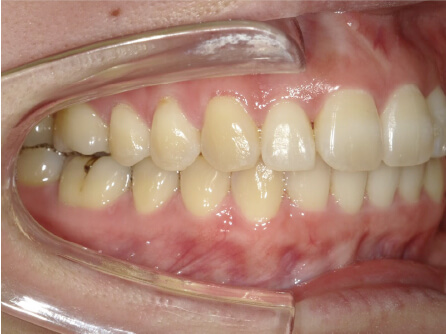

叢生の症例

41歳

女性

相談内容

正中がズレている。傾いている歯がある。

カウンセリング・診断結果

叢生・アレルギーなし・ext、IPR、アタッチメント、ミニスクリュー、ゴム掛け承諾

治療内容・方法

全額アライナー矯正・左下7セラミックはそのまま進めていく

術後の経過・現在の様子

クリアライナー使用

治療のリスク

痛み・歯根吸収・歯肉退縮・虫歯・後戻り

費用・治療期間

880,000円、1年9ヶ月